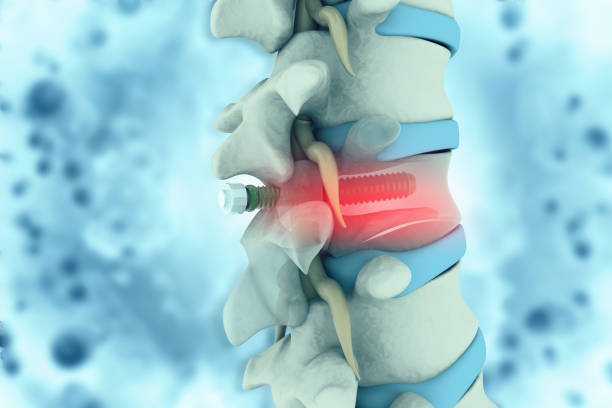

척추관협착증은 척추의 퇴행성 변화로 인해 발생합니다.

이 질환은 척추 내의 신경관이 좁아지면서 다양한 증상을 일으킵니다.

척추관협착증 치료방법 (신경 주사와 시술)

- 신경 주사는 스테로이드를 포함할 수 있으며, 적절한 사용 시 큰 부작용 없이 효과적입니다.

- 시술은 수술을 대체하는 것이 아니며, 신경 주위에 약물을 효과적으로 전달하는 방법입니다.